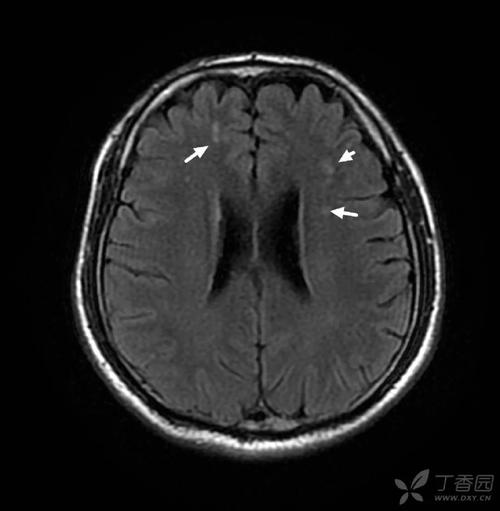

- 影像学表现:在磁共振上,这些病灶通常表现为点状、斑片状的异常信号,边界比较模糊,它们往往是陈旧性的,意味着是长期累积形成的,而不是急性发生的。

- 俗称:在医学上,这种由小血管病变引起的广泛白质改变,也常被称为“脑白质疏松”(Leukoaraiosis)或“慢性缺血性白质脑病”,在中老年人群中非常常见,很多人没有任何症状,只是在体检做头颅MRI时偶然发现。